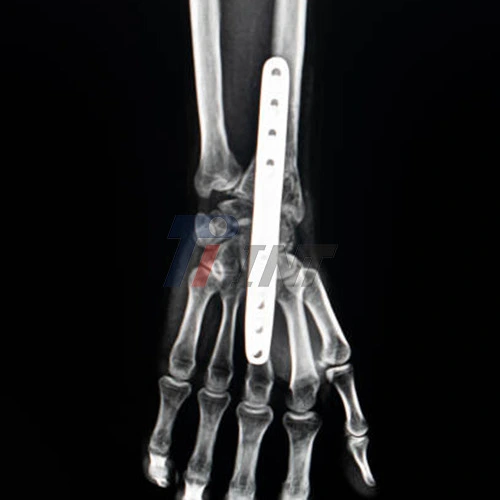

Another significant advantage of titanium plates is their radiolucency. This characteristic allows for clear visibility on X-rays and other imaging studies, enabling surgeons to accurately assess the fracture's alignment and healing progress without the plate obscuring the view. This transparency to radiation also facilitates postoperative monitoring and ensures that any complications can be detected early.

Using specialized surgical drills, the surgeon creates pilot holes in the bone for the screws that will secure the plate. The titanium screws are then inserted through the plate and into the bone, effectively anchoring the plate and holding the fracture fragments in their correct positions. The number and placement of screws vary depending on the fracture's complexity and the chosen plate design.

Throughout the procedure, the surgeon may use intraoperative fluoroscopy – real-time X-ray imaging – to confirm proper plate placement and fracture reduction. This technology allows for immediate adjustments if necessary, increasing the likelihood of a successful outcome.